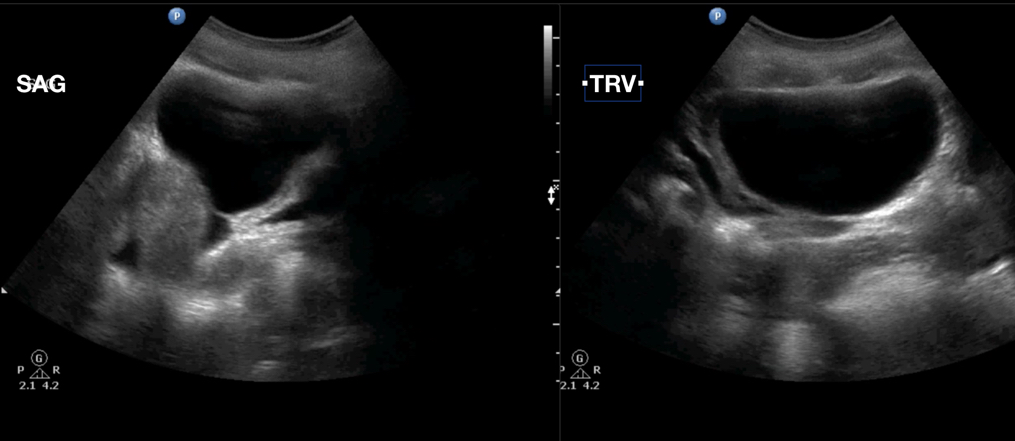

Pelvic Free Fluid In Patient With Diffuse Fluid And No Distant Air Download Scientific Diagram

Pelvic Free Fluid In Patient With Diffuse Fluid And No Distant Air Download Scientific Diagram from www.researchgate.net